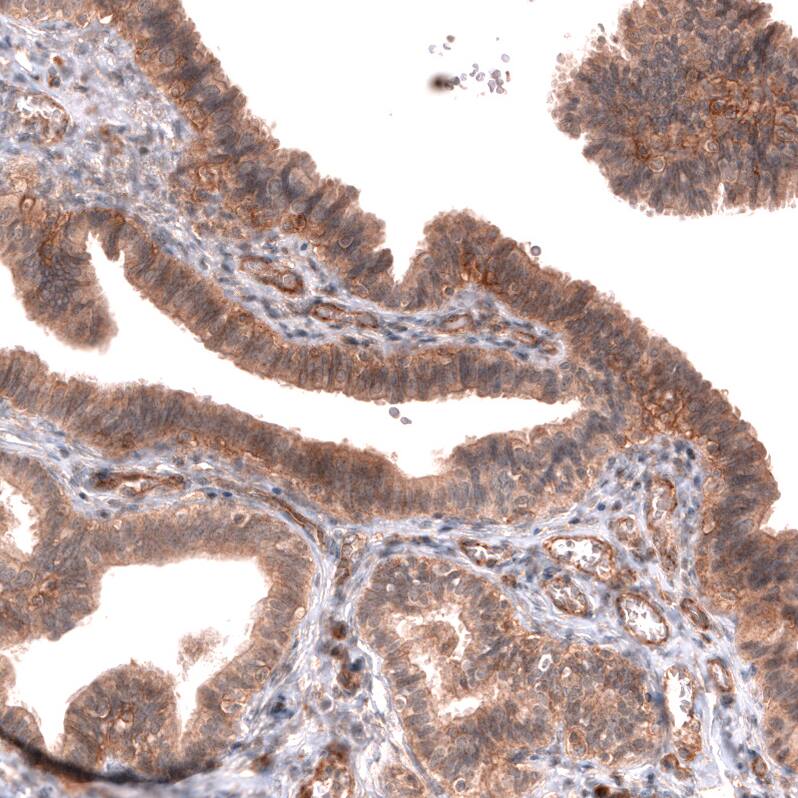

FXYD5/Dysadherin Antibody (CL14037) - Azide and BSA Free Immunohistochemistry-Paraffin: FXYD5/Dysadherin Antibody [NBP3-43835]

Immunohistochemistry-Paraffin: FXYD5/Dysadherin Antibody [NBP3-43835]

Staining of human fallopian tube shows moderate membranous and cytoplasmic positivity in glandular cells.